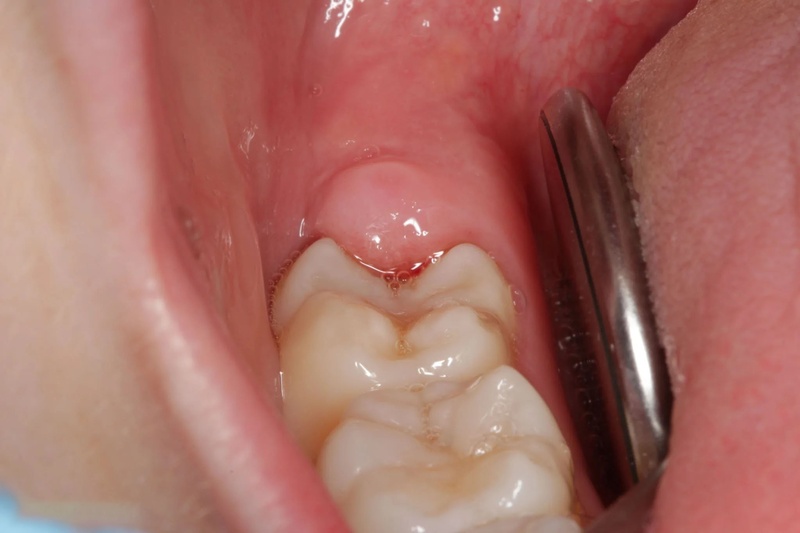

– Viêm lợi trùm: Hiện tượng phần lợi phía trong hàm bao phủ lên bề mặt răng khôn, khiến chúng kẹt lại, không thể tiếp tục trồi lên. Để khắc phục, bác sĩ chỉ định nhổ răng khôn hoặc cắt lợi trùm, tùy tình trạng mỗi người.